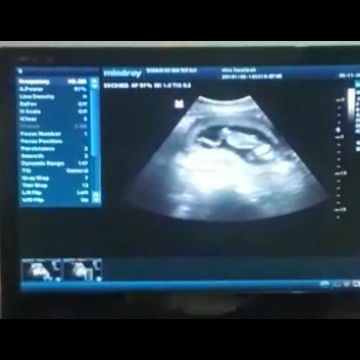

USG

Ini kebesaran gak sih untuk UK 15week ? Si baby lagi tengkurep ?